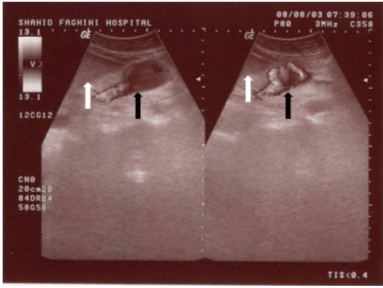

A 73-year-old female came to our sonogrphic clinic for abdomino-pelvic sonography as a routine work-up. In her medical history she had positive history of mild hyperlipidemia and mild essential hypertension and was on ß-blocker, nitroglycerine and anti-lipid therapy. Routine workup (CBC, LFT) was normal. She had no history of abdominal trauma or liver disease. Incidentally, on evaluation of para-aortic area, an anechoic structure was noted anterior to inferior vena cave (IVC) which was in continuation to portal confluence and was in the region of superior mesenteric vein (Figure 1). There was no sign of portal hypertension. Liver and spleen were normal (Figure 2). Color doppler flow mapping revealed flow inside the structure (Figure 3). Spectral analysis further confirmed venous type flow in this region (Figure 4). These findings confirmed the diagnosis of superior mesenteric vein aneurysm.

Figure 1: 73-year-old female asymptomatic patient with superior mesenteric vein aneurysm. Abdominal ultrasonography (GE Healthcare logic 500 convex probe 3.5 MHz) showed anechoic structure anterior to aorta. Normal diameter portal confluence (black arrow head), superior mesenteric artery (black arrows), normal diameter splenic vein (white arrowhead), aorta (long arrows), head of pancreas (curved arrow), dilated superior mesenteric vein (between white arrows).